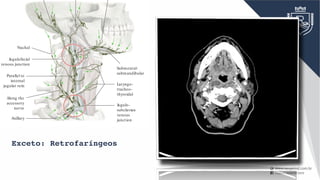

Exceto: Retrofaríngeos

ThoracicRight Jugulo- subclavian venous junction Laryngo- tracheo- thyroidal Submental- submandibular Nuchal Jugulofacial venous junction Parallel to internal jugularvein Along the accessory nerve Axillary C Directions of lymphatic drainage in the neck Right lateral view. The principal pattern of lymphatic ow in the neck is depicted. Understanding this pattern is critical to identifying the lo- cation of a potential cause of enlarged cervical lymph nodes. There are two main sites in the neck where the lymphatic pathways intersect: • The jugulofacial venous junction: Lymphatics from the head pass obliquely downward to this site, where the lymph is redirected verti- cally downward in the neck. • The jugulosubclavian venous junction: The main lymphatic trunk, the thoracic duct, terminates at this central location, where lymph col- lected from the left side of the head and neck region is combined with lymph draining from the rest of the body. If only peripheral nodal groups are a ected, this suggests a localized disease process. If the central groups (e.g., those at the venous junc- tions) are a ected, this usually signi es an extensive disease process. Central lymph nodes can be obtained for diagnostic evaluation by pres- calene biopsy. Exceto: Retrofaríngeos